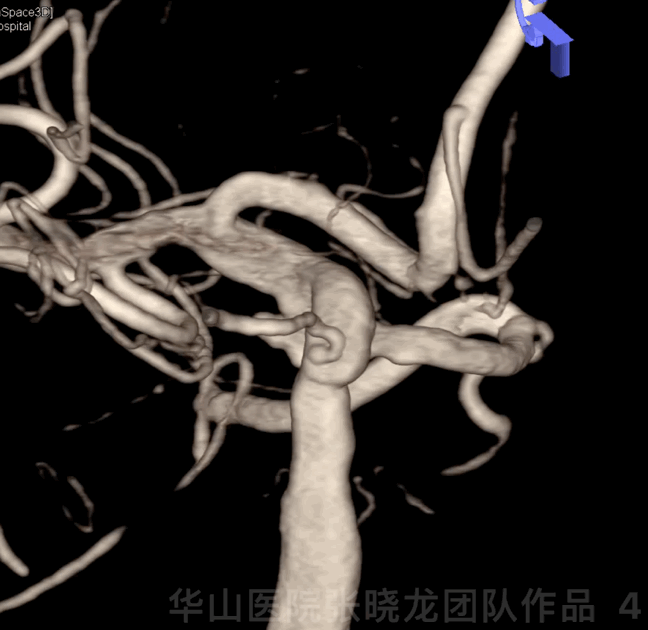

Figure 4 GIF. 3D reconstruction clearly showed the right lobular wide-necked posterior communicating artery aneurysm.

图 4 GIF. 3D重建示右侧后交通宽颈动脉瘤呈分叶状。